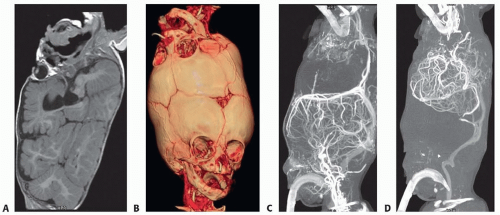

Detailed multimodality imaging provides key information for general management and is essential for surgical planning (FIG 3).7

CT: Visualizes bony morphology, sutural pattern, and the relationship of the brain, skin, and dura to the skull

MRI: Delineates brain and dural anatomy indicating areas of possible cortical fusion and dural defects

Digital subtraction angiography: Provides anatomical information about arterial and venous systems and the extent and direction of vascular crossover between the twins. This modality also characterizes the relationship between the deep and superficial venous drainage systems of the brain for planning separation.

CT angiography: Characterizes the anatomy of the dural venous sinuses